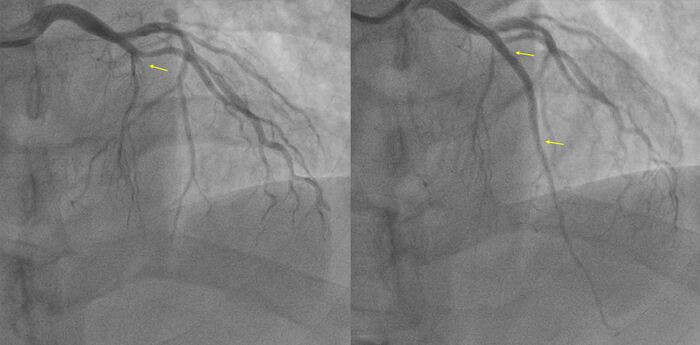

С учетом данных ВСУЗИ проводится сразу прямое (без предварительной предилатации баллоном) стентирование ПМЖА с покрытием ствола левой коронарной артерии.

Получаем такой результат

Клинически тоже все хорошо, на следующие сутки переведена в отделение. Готовится к выписке.